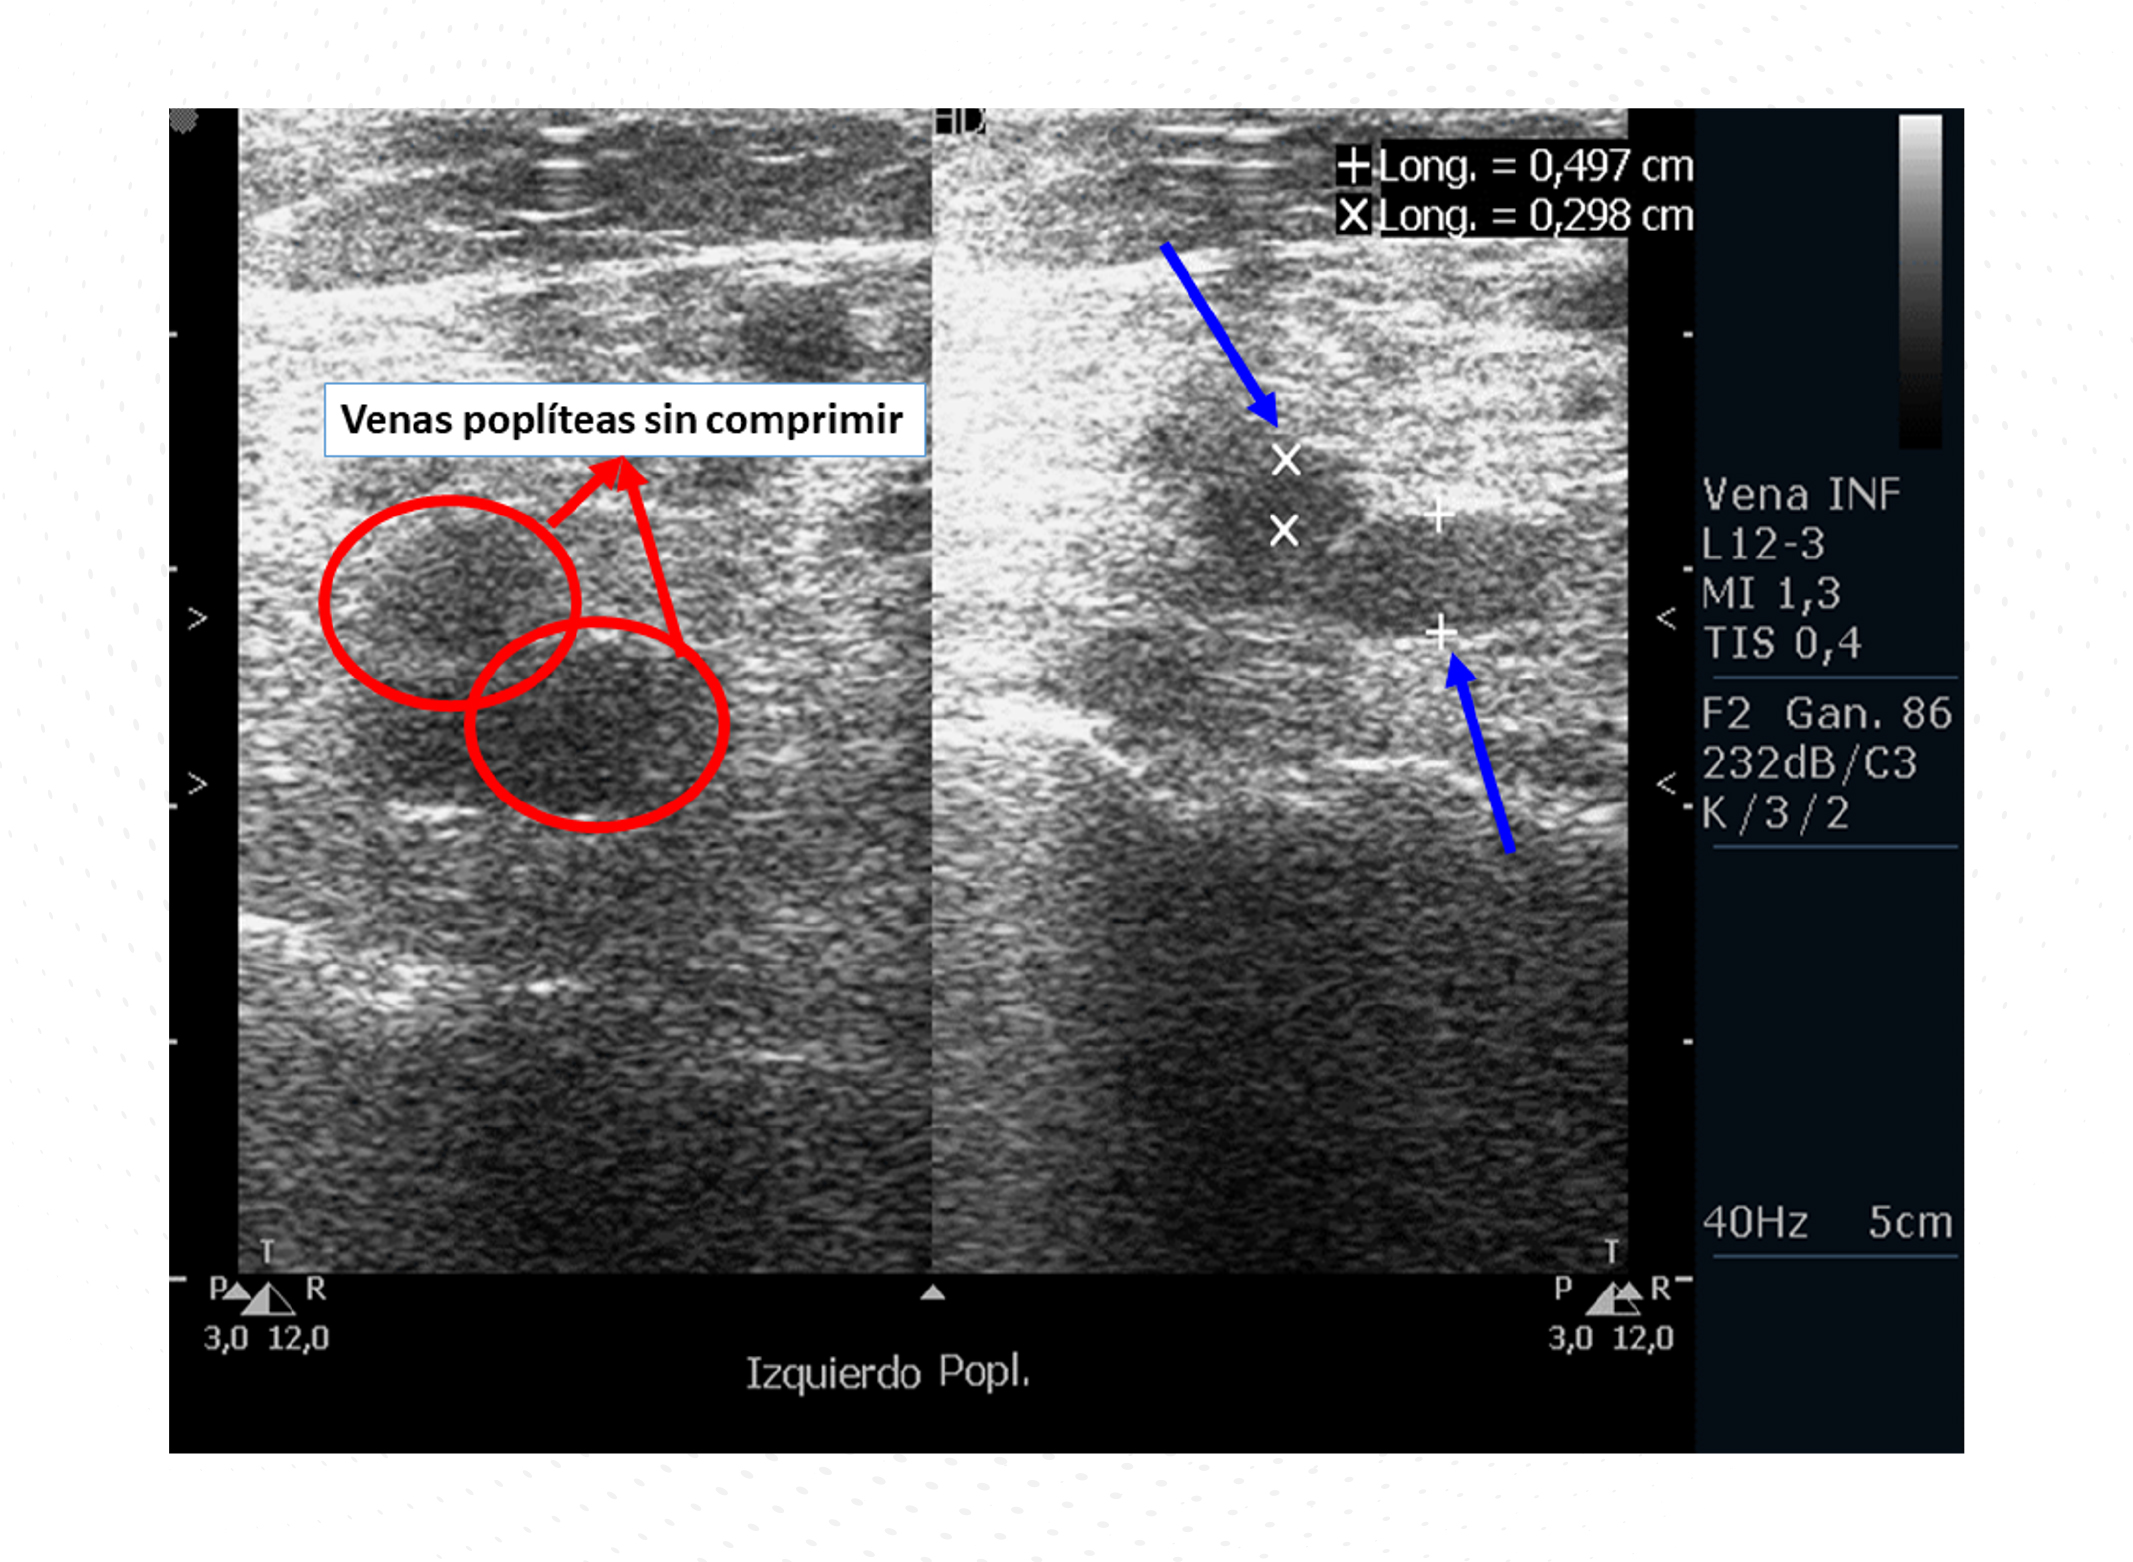

Durante los siguientes meses continuó con tratamiento quimioterápico y con bemiparina sin presentar ningún tipo de complicación relacionada con el tratamiento. Un año después, la paciente comenzó con síntomas neurológicos, por lo que se decidió su ingreso hospitalario para estudio. Tanto la exploración física como la analítica estaban dentro de la normalidad, aunque la exploración neurológica manifestó inestabilidad de la marcha, cansancio severo y torpeza con las extremidades inferiores sin foco neurológico claro, cefalea, dolor, fiebre o cualquier otro síntoma. Se realizó una tomografía computarizada (TC) craneal que mostró múltiples lesiones ocupantes de la estación en todo el cerebro compatibles con metástasis cerebrales del cáncer de mama primario con edema perilesional (Figura 2). Ante esos hallazgos, la paciente comenzó tratamiento con dexametasona (8 mg cada 8 horas) y se programaron 10 sesiones de radioterapia holocraneal. El dilema que se planteó con la paciente radicaba en el manejo del tratamiento anticoagulante.